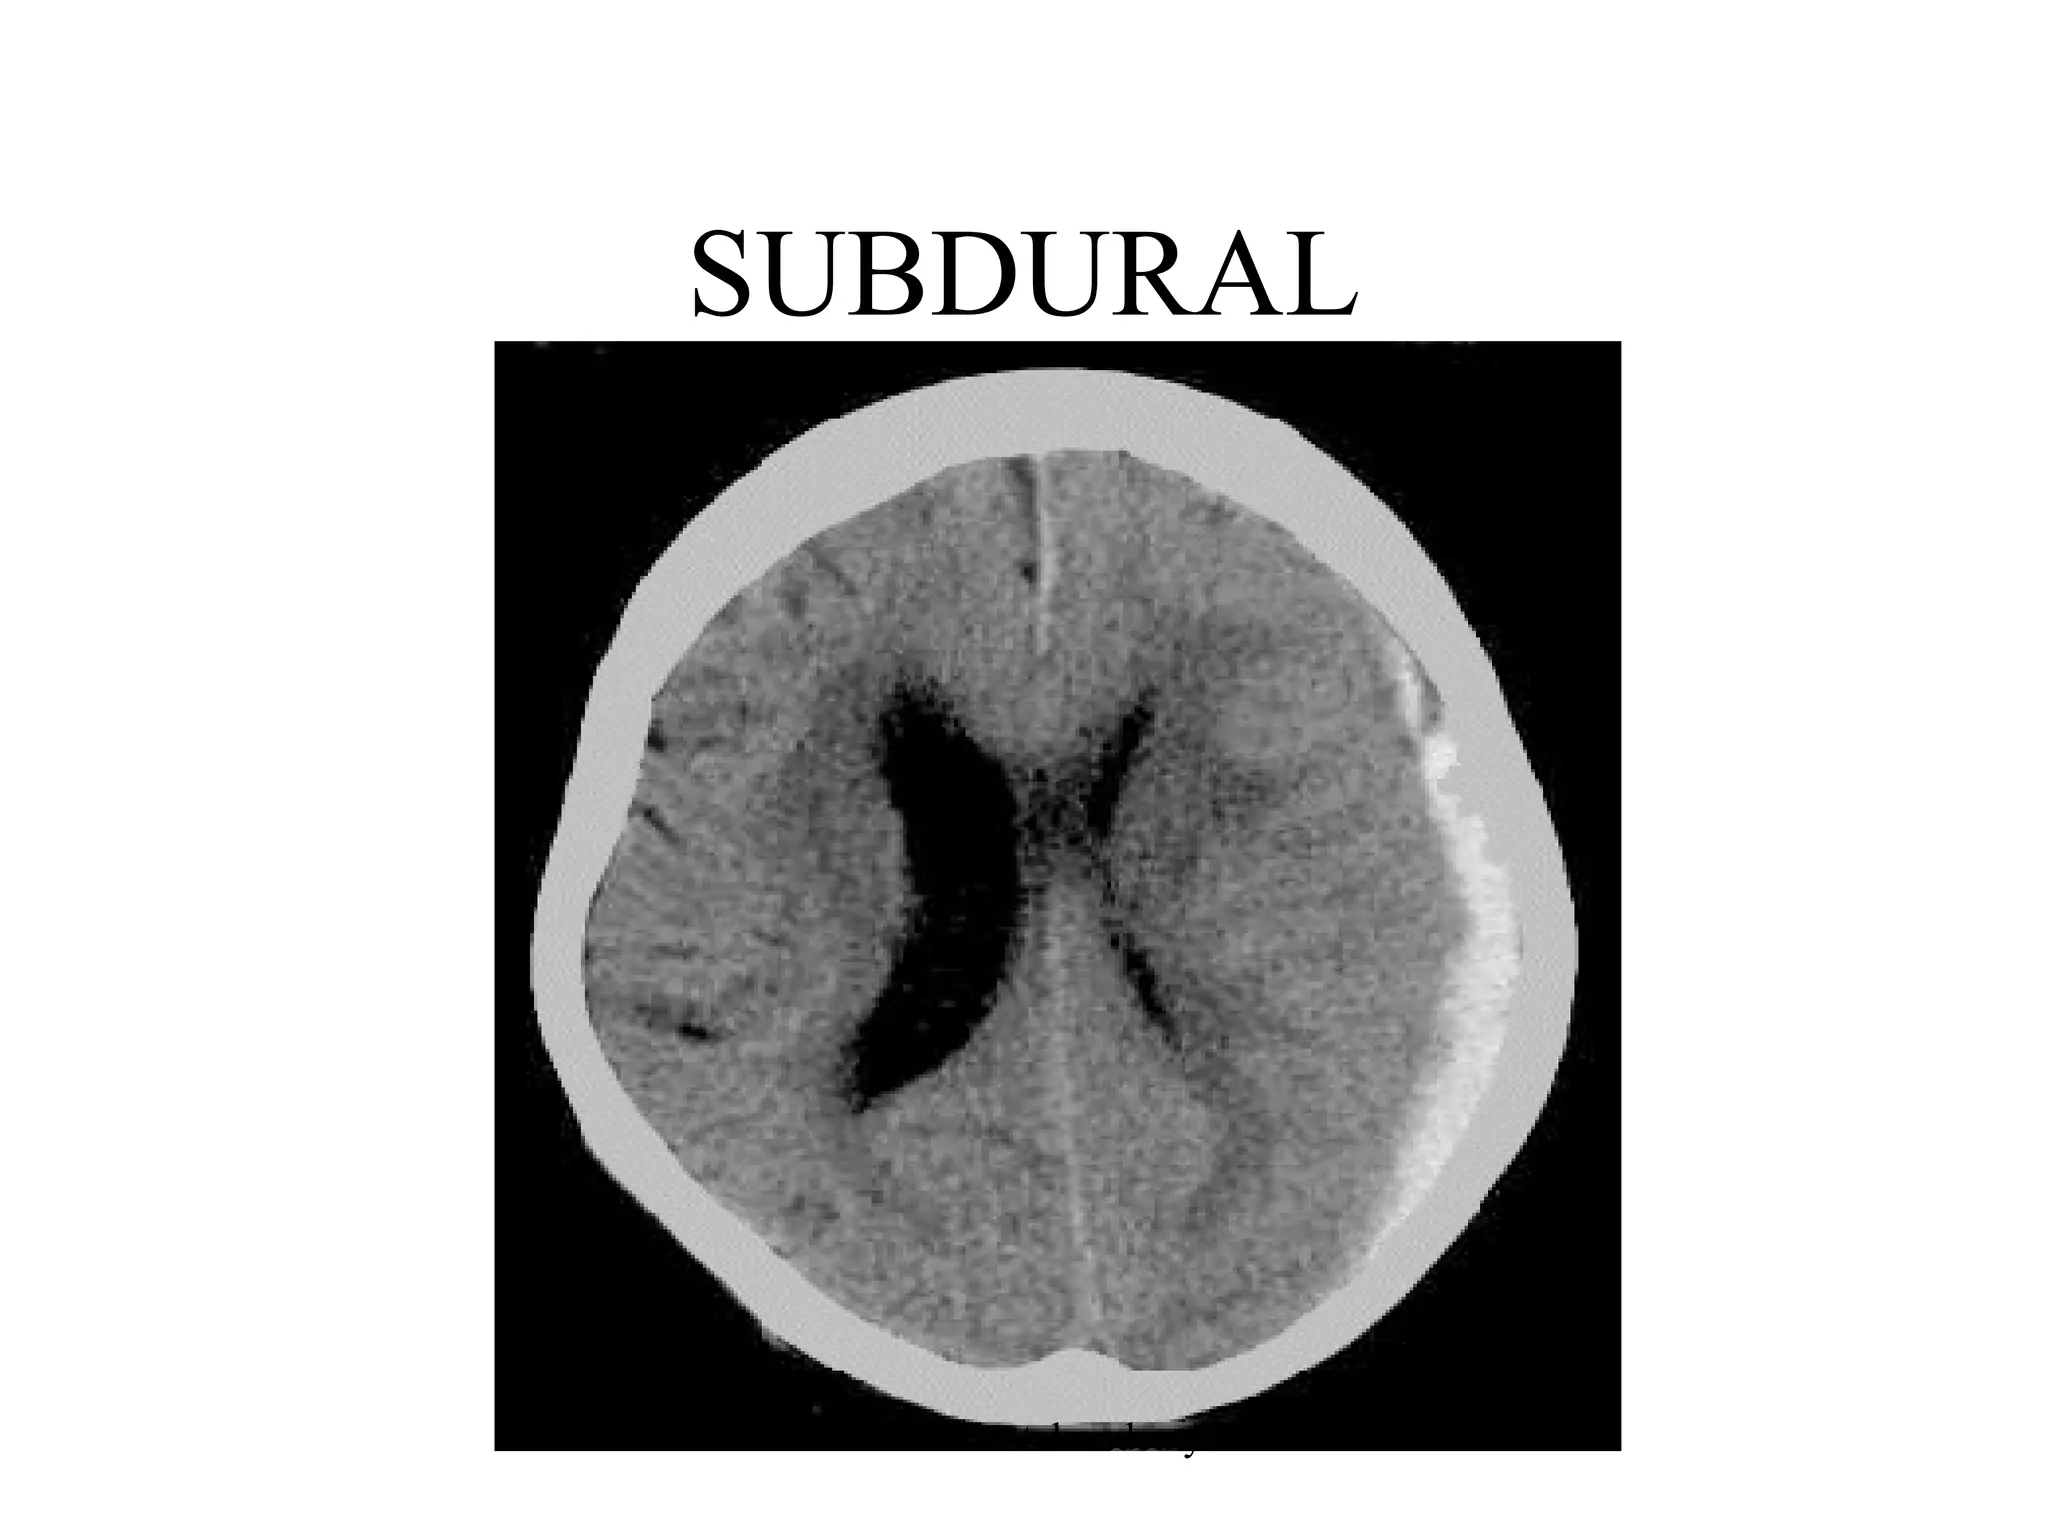

SUBDURAL

www.indiandentalacademy.com

SDH

• form of traumatic brain injury in which

blood gathers between the dura (the outer

protective covering of the brain) and the

arachnoid (the middle layer of the

meninges).